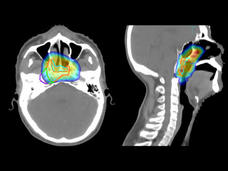

El toripalimab es el primer medicamento de inmunoterapia aprobado para el cáncer de nasofaringe

La Administración de Alimentos y Medicamentos (FDA) aprobó el toripalimab (Loqtorz) a partir de los resultados de un estudio clínico grande en el que se demostró que añadirlo a la quimioterapia prolongó la supervivencia de las personas con cáncer de nasofaringe que volvió después del tratamiento inicial o se diseminó.